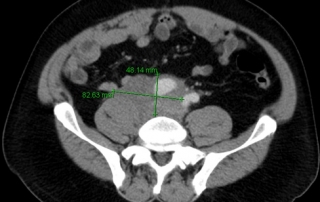

Biologie : hémogramme normal, augmentation des LDH à 680 UI pour une limite supérieure de la normale à 250 UI, sur la biopsie médullaire présence d’une infiltration par le lymphome à grandes cellules.

Classement : lymphome diffus à grandes cellules B CD20+ stade IV médullaire et péritoine, indice OMS = 0, LDH augmentées, IPIaa = 2.

Décision traitement initial par R-ACVBP x 4 cycles avec prophylaxie neuro-méningée et consolidation par méthotréxate à hautes doses x 2 cycles plus conditionnement autogreffe sous réserve d’obtention d’une rémission complète après R-ACVBP. En cas de réponse partielle, indication d’un contrôle histologique. En l’absence d’essai thérapeutique ouvert au moment du diagnostic, un traitement guidé par la TEP-FDG précoce après 2 cycles de R-ACVBP, n’est pas recommandé par la RCP.

Décision consolidation par méthotréxate et conditionnement BEAM autogreffe de CSH.

Evaluation réalisée 3 mois après autogreffe par scanner et TEP-FDG confirmait la rémission complète.